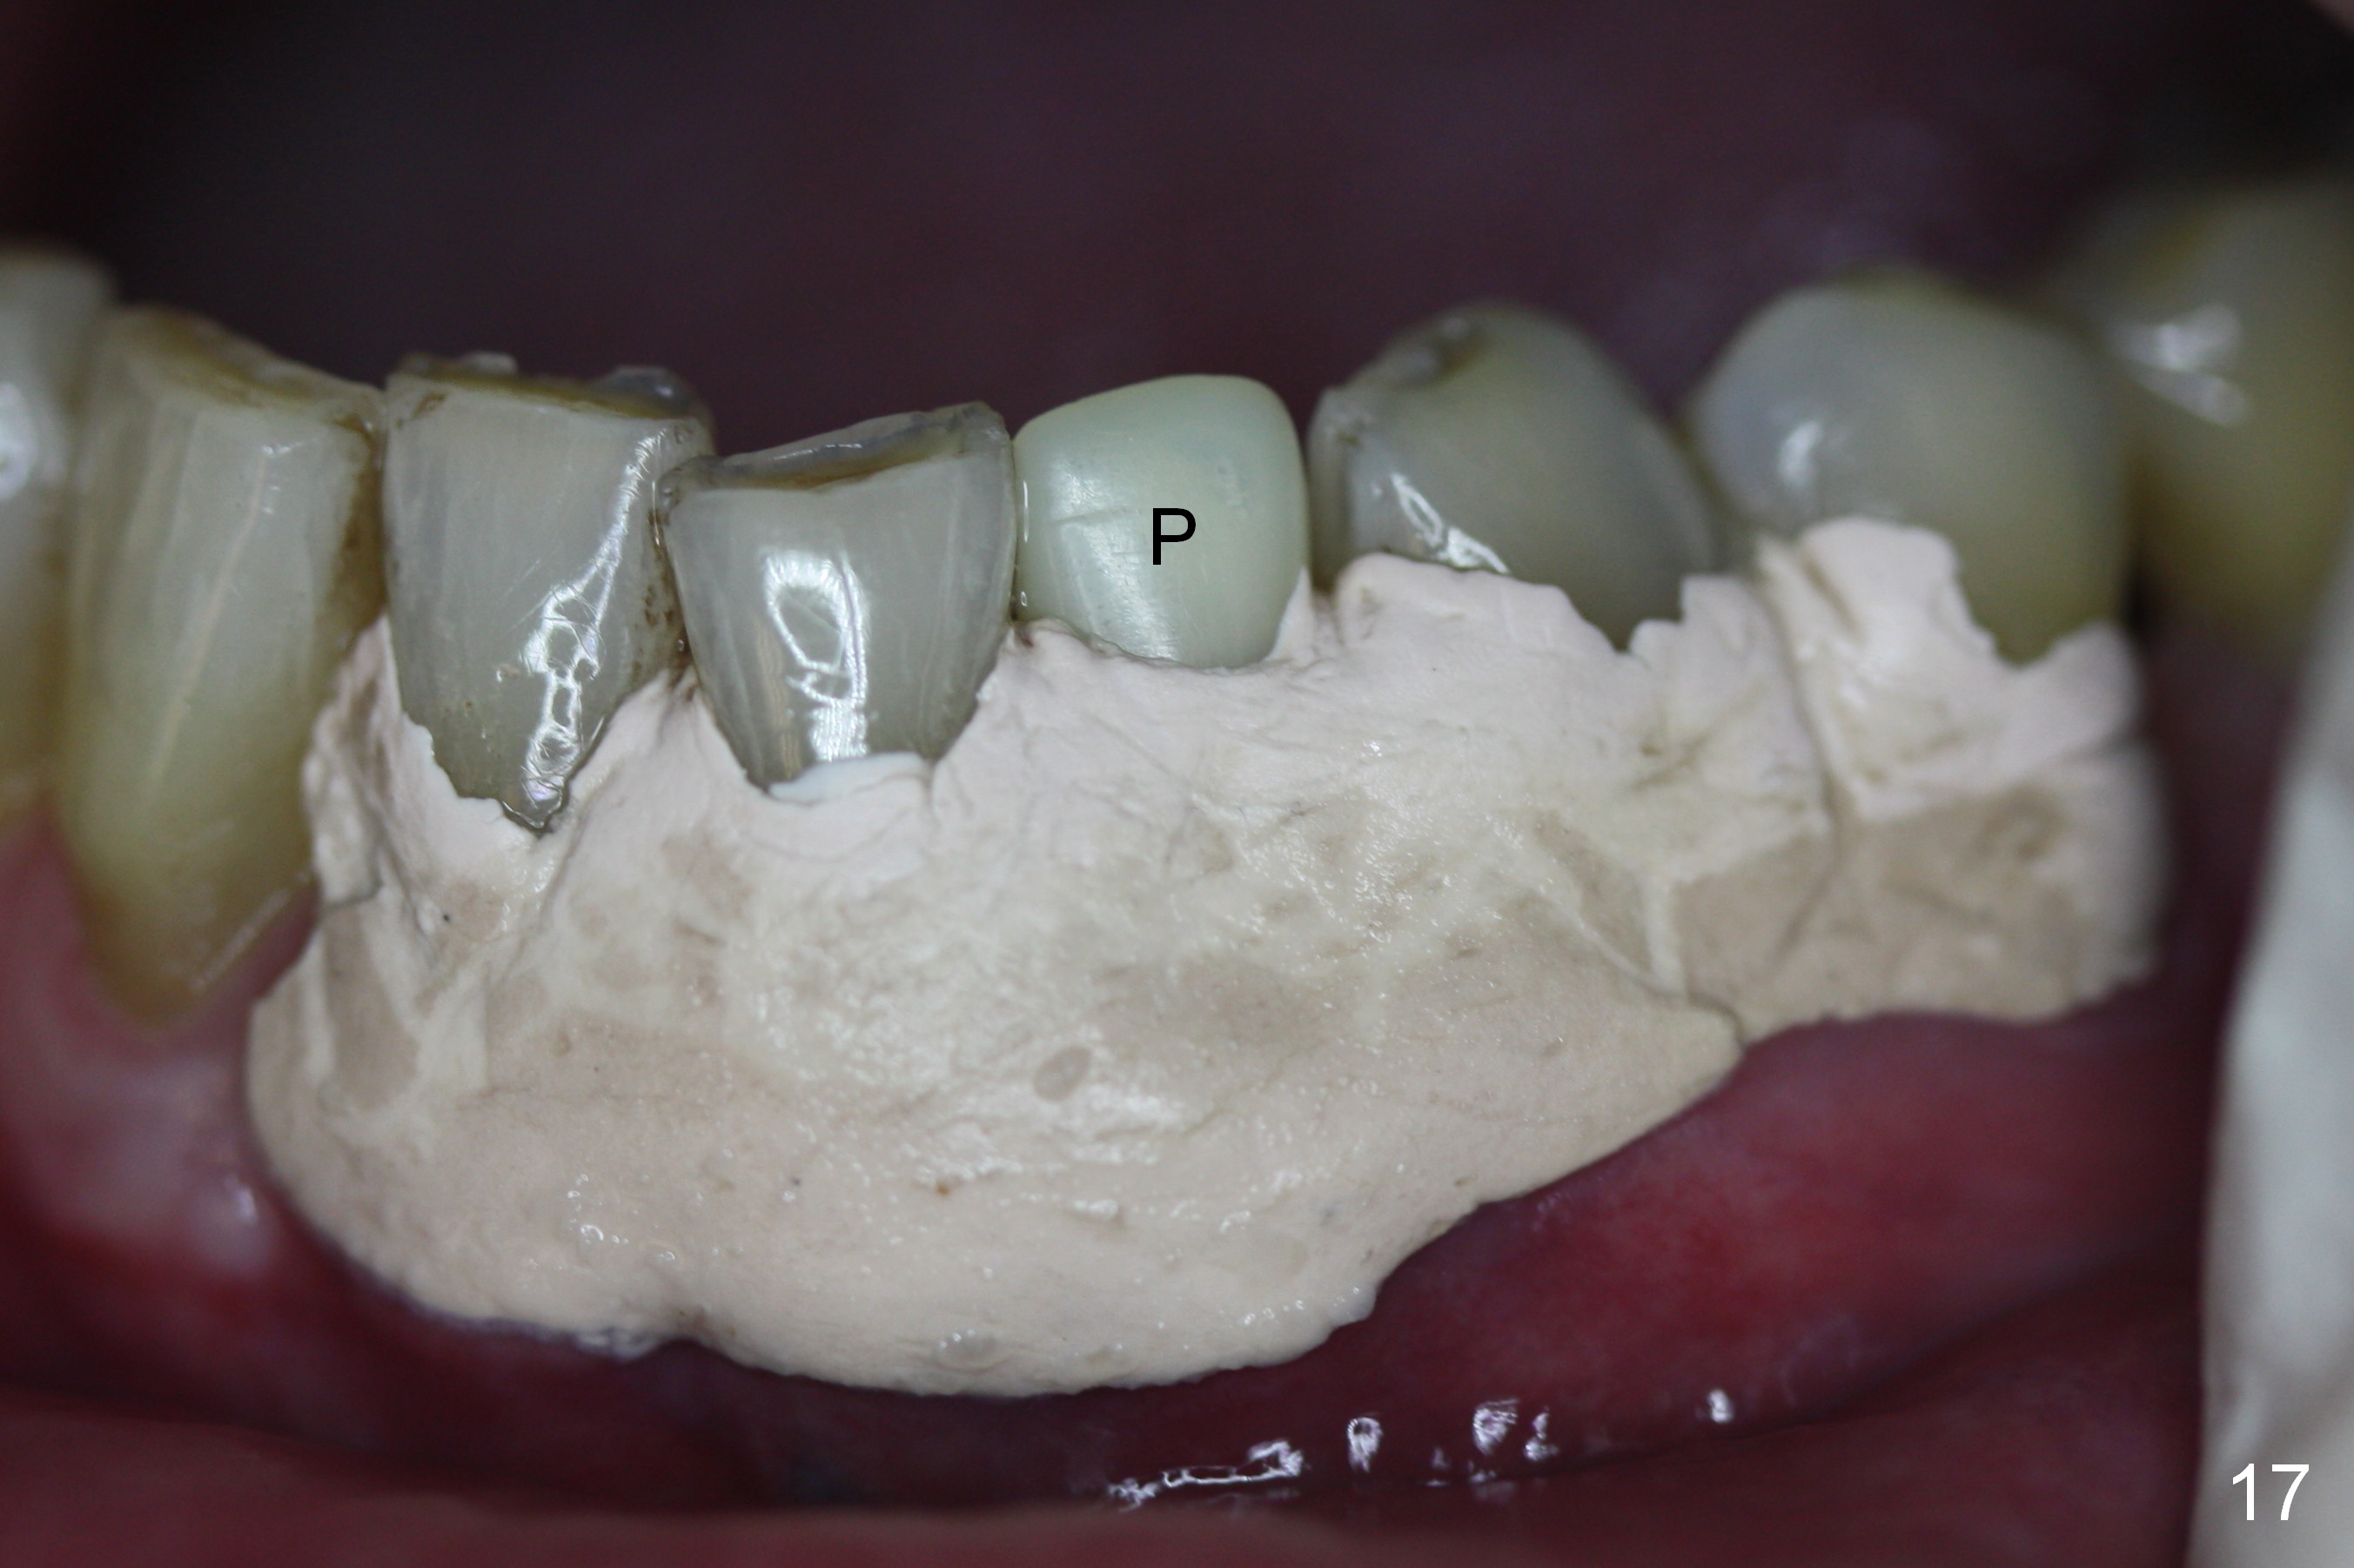

A 74-year-old man has several missing teeth (Fig.1).  His 1st goal is to replace the lower left lateral incisor (Fig.2).  The residual root has an apical lesion (Fig.3 *).  To describe intraop findings, a CT image of a different patient is used (Fig.4 coronal section; B: buccal; L: lingual).  After extraction, the buccal plate is found to be thin and low (Fig.5 arrowheads).  A 1.5 mm pilot drill (Fig.6 red line) is used to initiate osteotomy in the lingual plate of the socket.  Once the drill penetrates the lingual plate, the trajectory changes and the depth is 17 mm from the gingival margin (Fig.7).  A PA is taken (Fig.8); it appears that the osteotomy can be extended more apically.  When the pilot drill extends to 20 mm, there is sudden empty feeling.  The lingual plate has perforated (Fig.9).  A new osteotomy is established buccally (Fig.10 pink).  To avoid buccal plate perforation, especially in the buccal undercut area (>), the coronal end of the drill has to be tilted buccally (<--).  An angled abutment (3x20 mm, 15°) is placed (Fig.11,12).  The abutment is modified (Fig.13,14) to accommodate an immediate provisional (Fig.15,16 P).  Perio dressing is to be applied to prevent the bone graft from getting dislodged buccally (Fig.15).  The dressing is in place 7 days postop (Fig.17).

Five months postop, the peri-implant space reduces (Fig.18).  A keratinized band forms buccal to the implant (Fig.19 *).  The provisional dislodges probably due to the buccal placement (Fig.20).